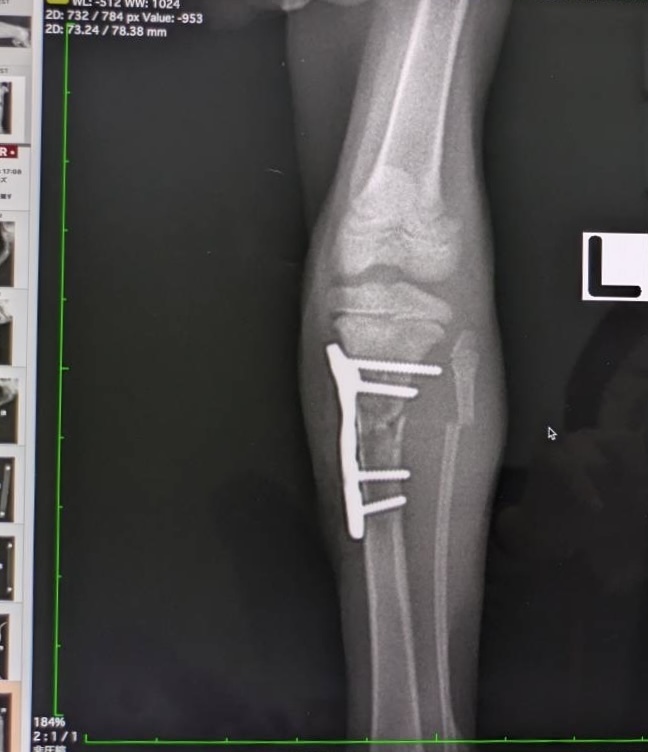

【左足 術後】

【本日】骨が太く隙間なく癒合しています。腓骨(細い方)も太く真っ直ぐになりました。